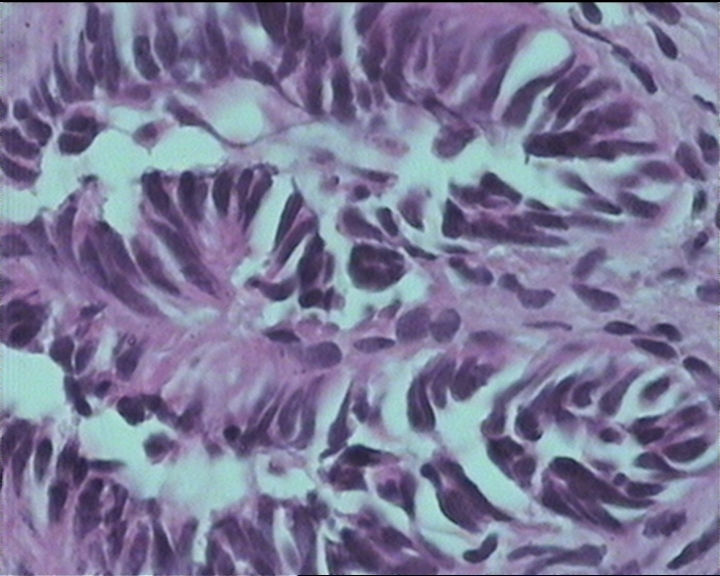

54岁女性,临床“宫颈息肉”送检;巨检:组织一块1。5*1CM,灰红。

输卵管粘膜化生

It is benign. Benign endocervical polyp with tubal metaplasia.

细胞及腺体均有异形,图6、11、16象有纤维间质反应,考虑高级别上皮内瘤变/原位癌,腺癌不能除外。

Sternberg病理学上诊断宫颈原位腺癌的标准是腺体的上皮去粘液分化,呈乳头状或筛网状增生,核分裂易见,这例显然达不到此标准。此例还是归入到腺上皮不典型增生为好。

杨老师说它是良性的,是个颈管内膜息肉伴输卵管上皮化生,良性